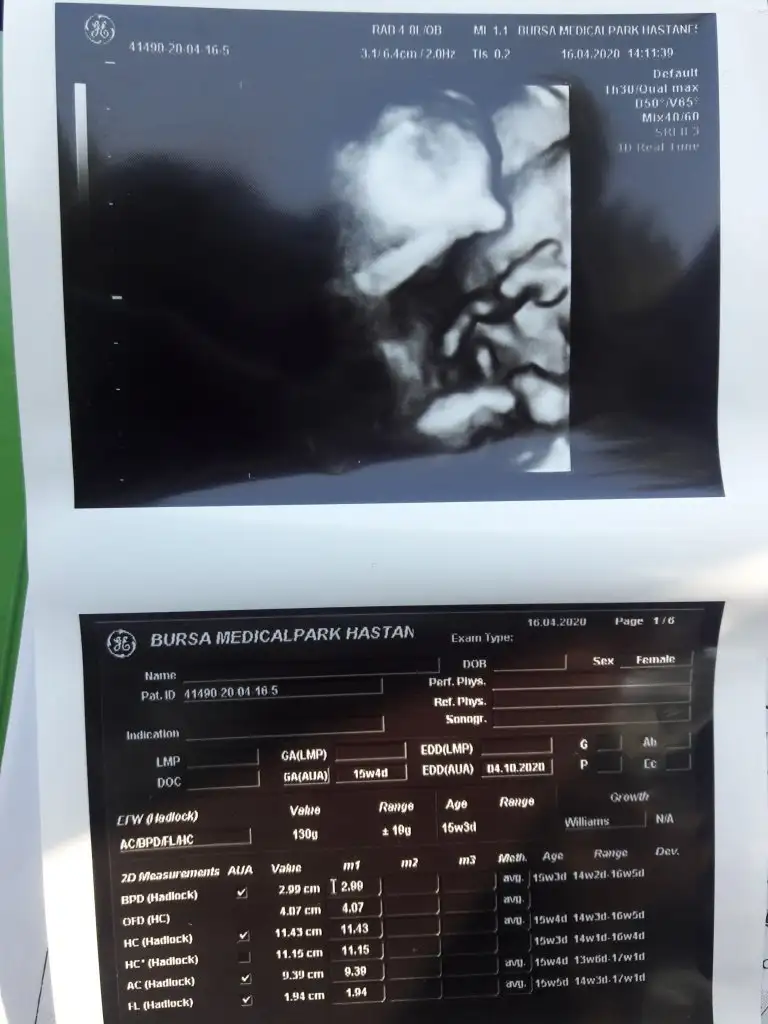

Kaç haftalık 11 12 13 hafta olmalı nublar kapalı kafa yapısı erkek gibi tutmayabilir nub için istediğim haftalarıda paylaşınBenimde bebeğime bakarmısınız dr ters olduğu için göremedi Eki Görüntüle 2619582 Eki Görüntüle 2619582 Eki Görüntüle 2619583

13+2 haftalıkKaç haftalık 11 12 13 hafta olmalı nublar kapalı kafa yapısı erkek gibi tutmayabilir nub için istediğim haftalarıda paylaşın![]()

15+3